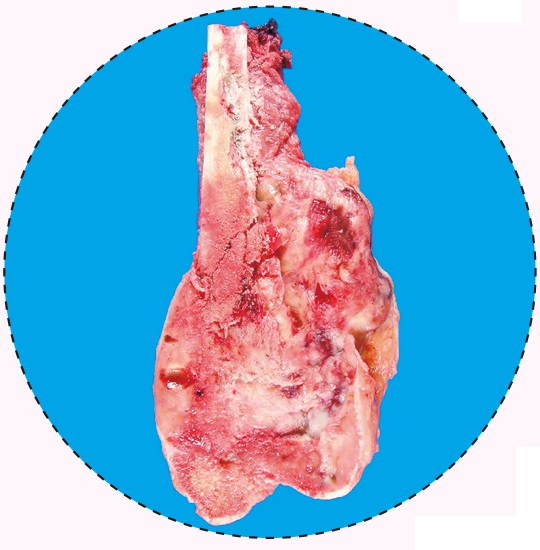

骨巨细胞瘤的病理图像

骨巨细胞瘤具有较强侵袭性,对骨质的溶蚀破坏作用大,容易造成病理性骨折,极少数有反应性新骨生成及自愈倾向,可穿过骨皮质形成软组织包块,刮除术后复发率高,少数可出现局部恶变或肺转移(即所谓良性转移)。骨巨细胞瘤为低度恶性或潜在恶性的肿瘤。